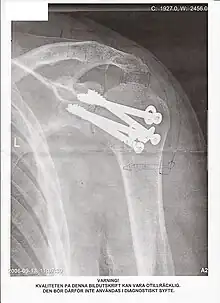

Une arthrodèse est une intervention chirurgicale destinée à bloquer une articulation lésée par l'obtention d'une fusion osseuse (en général de l'extrémité des os) dans le but de corriger une déformation ou d'obtenir l'indolence. C'est souvent une opération non réversible. L'opération inverse, qui consiste à désolidariser des os fusionnés, s'appelle une désarthrodèse.

L'arthrodèse de la cheville est souvent effectuée pour réparer cette articulation lorsqu'elle est atteinte d'arthrose, à la suite d'un accident (chirurgie post-traumatique), une usure (parfois liée à une activité professionnelle, ou une maladie dégénérative comme la poliomyélite), ou encore une malformation (pieds bots par exemple).

Elle implique la plupart du temps au moins l'astragale et le calcaneum. Suivant le nombre de fusions effectuées (et donc de degrés de liberté perdus), on parle d'arthrodèse simple, double ou triple.